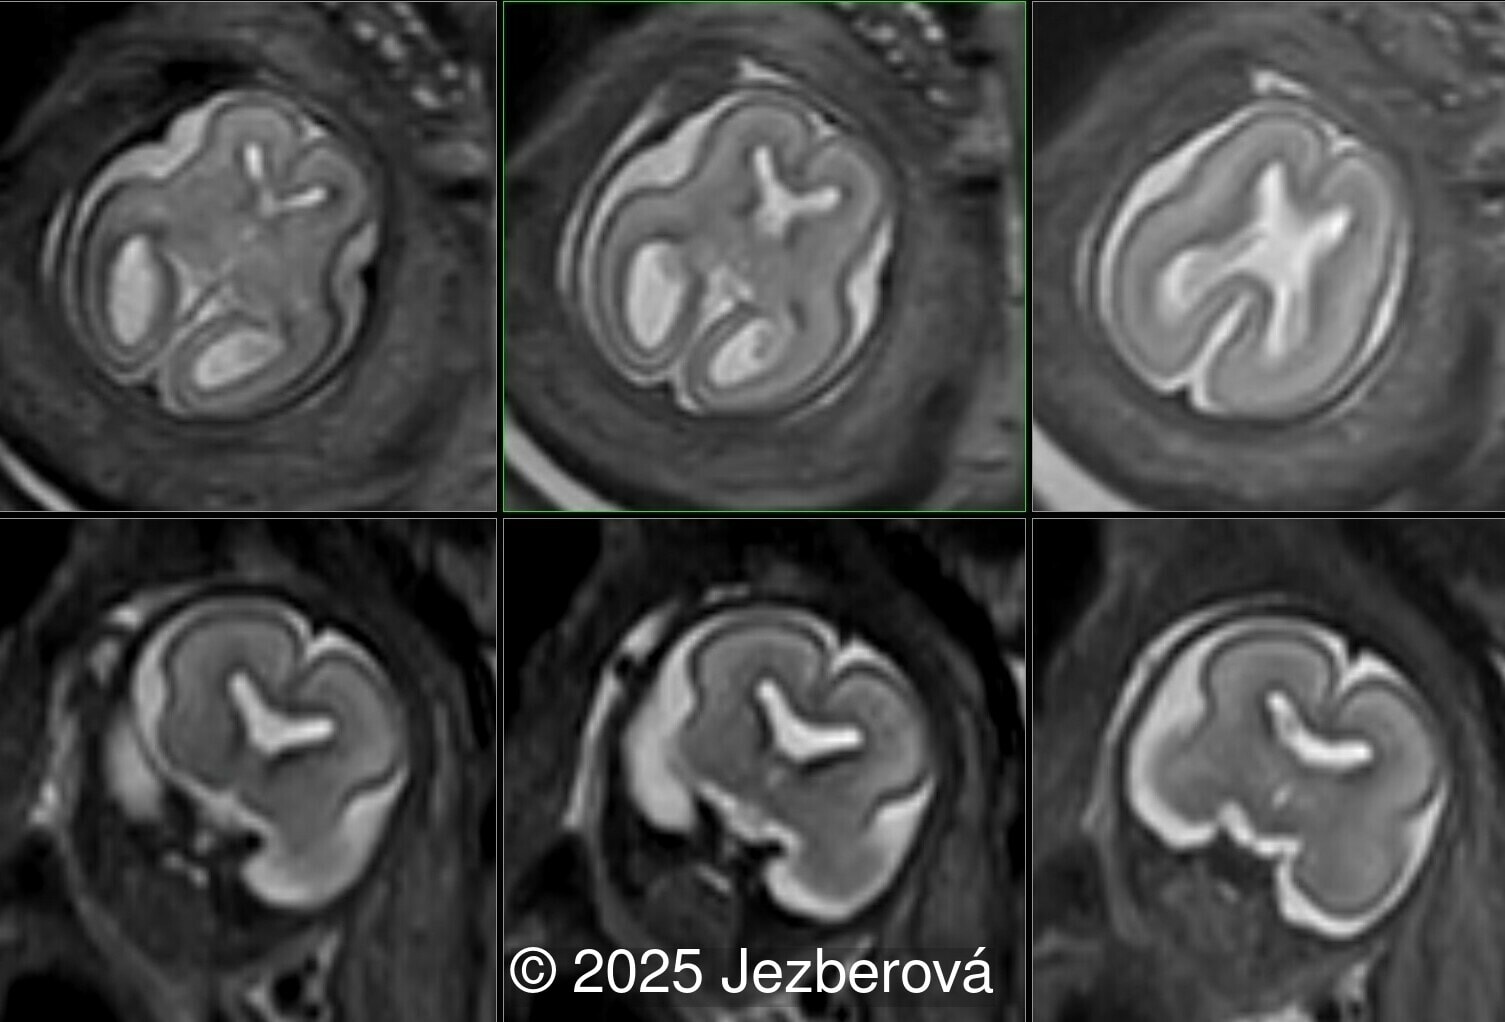

At 20 weeks, detailed ultrasound under conditions of severe oligohydramnios demonstrated absence of the typical box-shaped anechoic structure of the cavum septum pellucidum (CSP). The frontal horns of the lateral ventricles appeared narrow and pointed, giving the characteristic “bull’s horns sign.” Multiplanar and 3D reconstructions confirmed the presence of the corpus callosum, while the CSP was absent. Other midline and posterior fossa structures appeared normal. The optic chiasm was partially visualized, although assessment was limited by technical conditions. Fetal magnetic resonance imaging (MRI) was subsequently performed and confirmed isolated agenesis of the CSP with preserved corpus callosum and posterior fossa structures. The optic chiasm and pituitary stalk are visible in the sellar region, but the pituitary gland itself is not clearly identified in the sella turcica as it is a very small structure. No additional central nervous system anomalies were detected.